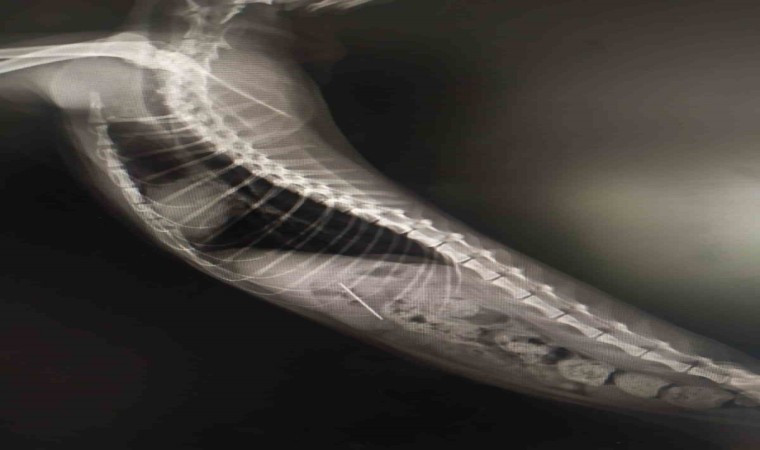

Bolu’da rahatsızlanarak veteriner hekime götürülen yaramaz kedinin midesinden, yuttuğu dikiş iğnesi çıktı.

Bolu’da kedisinin rahatsızlandığını fark eden bir kişi veteriner hekime başvurdu. Edinilen bilgiye göre, özel bir veteriner kliniğinde muayene edilen kedinin röntgeni çekildi. Kedinin midesinde dikiş iğnesi olduğu görüldü. Endoskopiyle dikiş iğnesi kedinin midesinden çıkartıldı. Bir süre veteriner kliniğinde müşahede altında tutulan kedi taburcu edildi.

Kedinin dikiş iğnesin yuttuğu öne sürüldü.